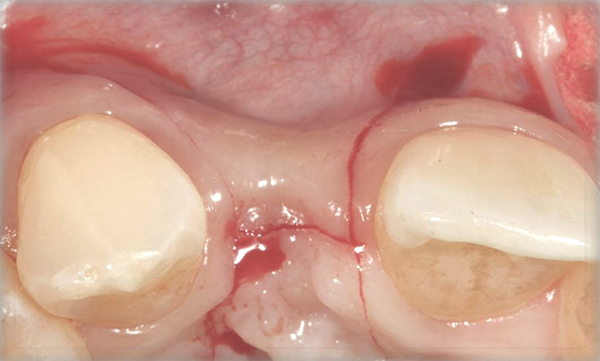

Fig 6. Collagen barrier positioned over bone graft.

Figure 6

In the esthetic zone it is preferable to avoid elevating papillae because flap elevation may induce recession and create unesthetic black triangles.4 If a flap is necessary to perform a procedure in an edentate area when adjacent teeth are present, the following technique can be used to circumvent blunting papillae. Make a horizontal incision along the midcrestal or palatal aspect of the ridge and terminate the incision 1 mm from the adjacent teeth (Figure 1). The incision is created palatally if it is desired to transpose keratinized tissue to the buccal. From the horizontal incision, create bilateral buccal vertical releasing incisions that extend obliquely at an angle (Figure 2). The vertical incisions can also be extended palatally (for access), but this is not always necessary (Figure 3). Preserved papillae contain gingival supracrestal fibers that subsequently help maintain papillary height (Figure 4). The distance the incision is extended vertically on the buccal is dictated by the task to be accomplished (eg, implant insertion only requires short vertical incisions, while bone grafting needs longer incisions) (Figure 5 and Figure 6). At the end of the surgical procedure, the severed papillary segments are sutured to their retained counterparts (Figure 7 and Figure 8). Figure 1 through Figure 8 demonstrate a submerged implant protocol.